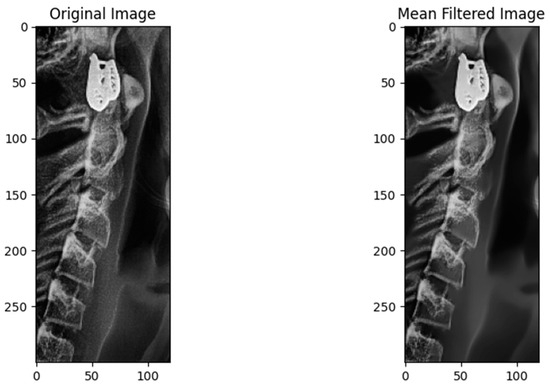

2.3.1. Reading Images

2.3.2. Preprocessing Step